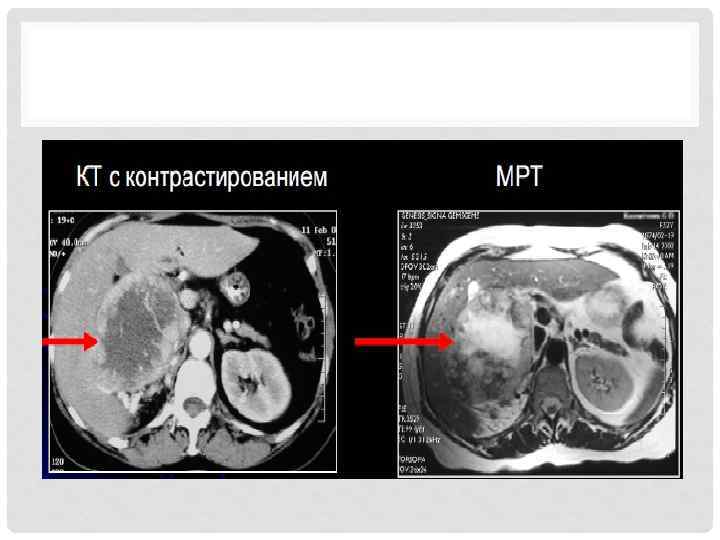

ДИАГНОСТИКА • Стандартные исследования. • Рентгенография ОГК ( большие округлые тени «пушечные ядра» ). • КТ. • МРТ. • Дуплексное УЗИ (опухолевый тромб). • Сцинтиграфия костей. • КТ головного мозга. • Чрескожная пункция (крайне редко). • Открытая биопсия или нефрэктомия.